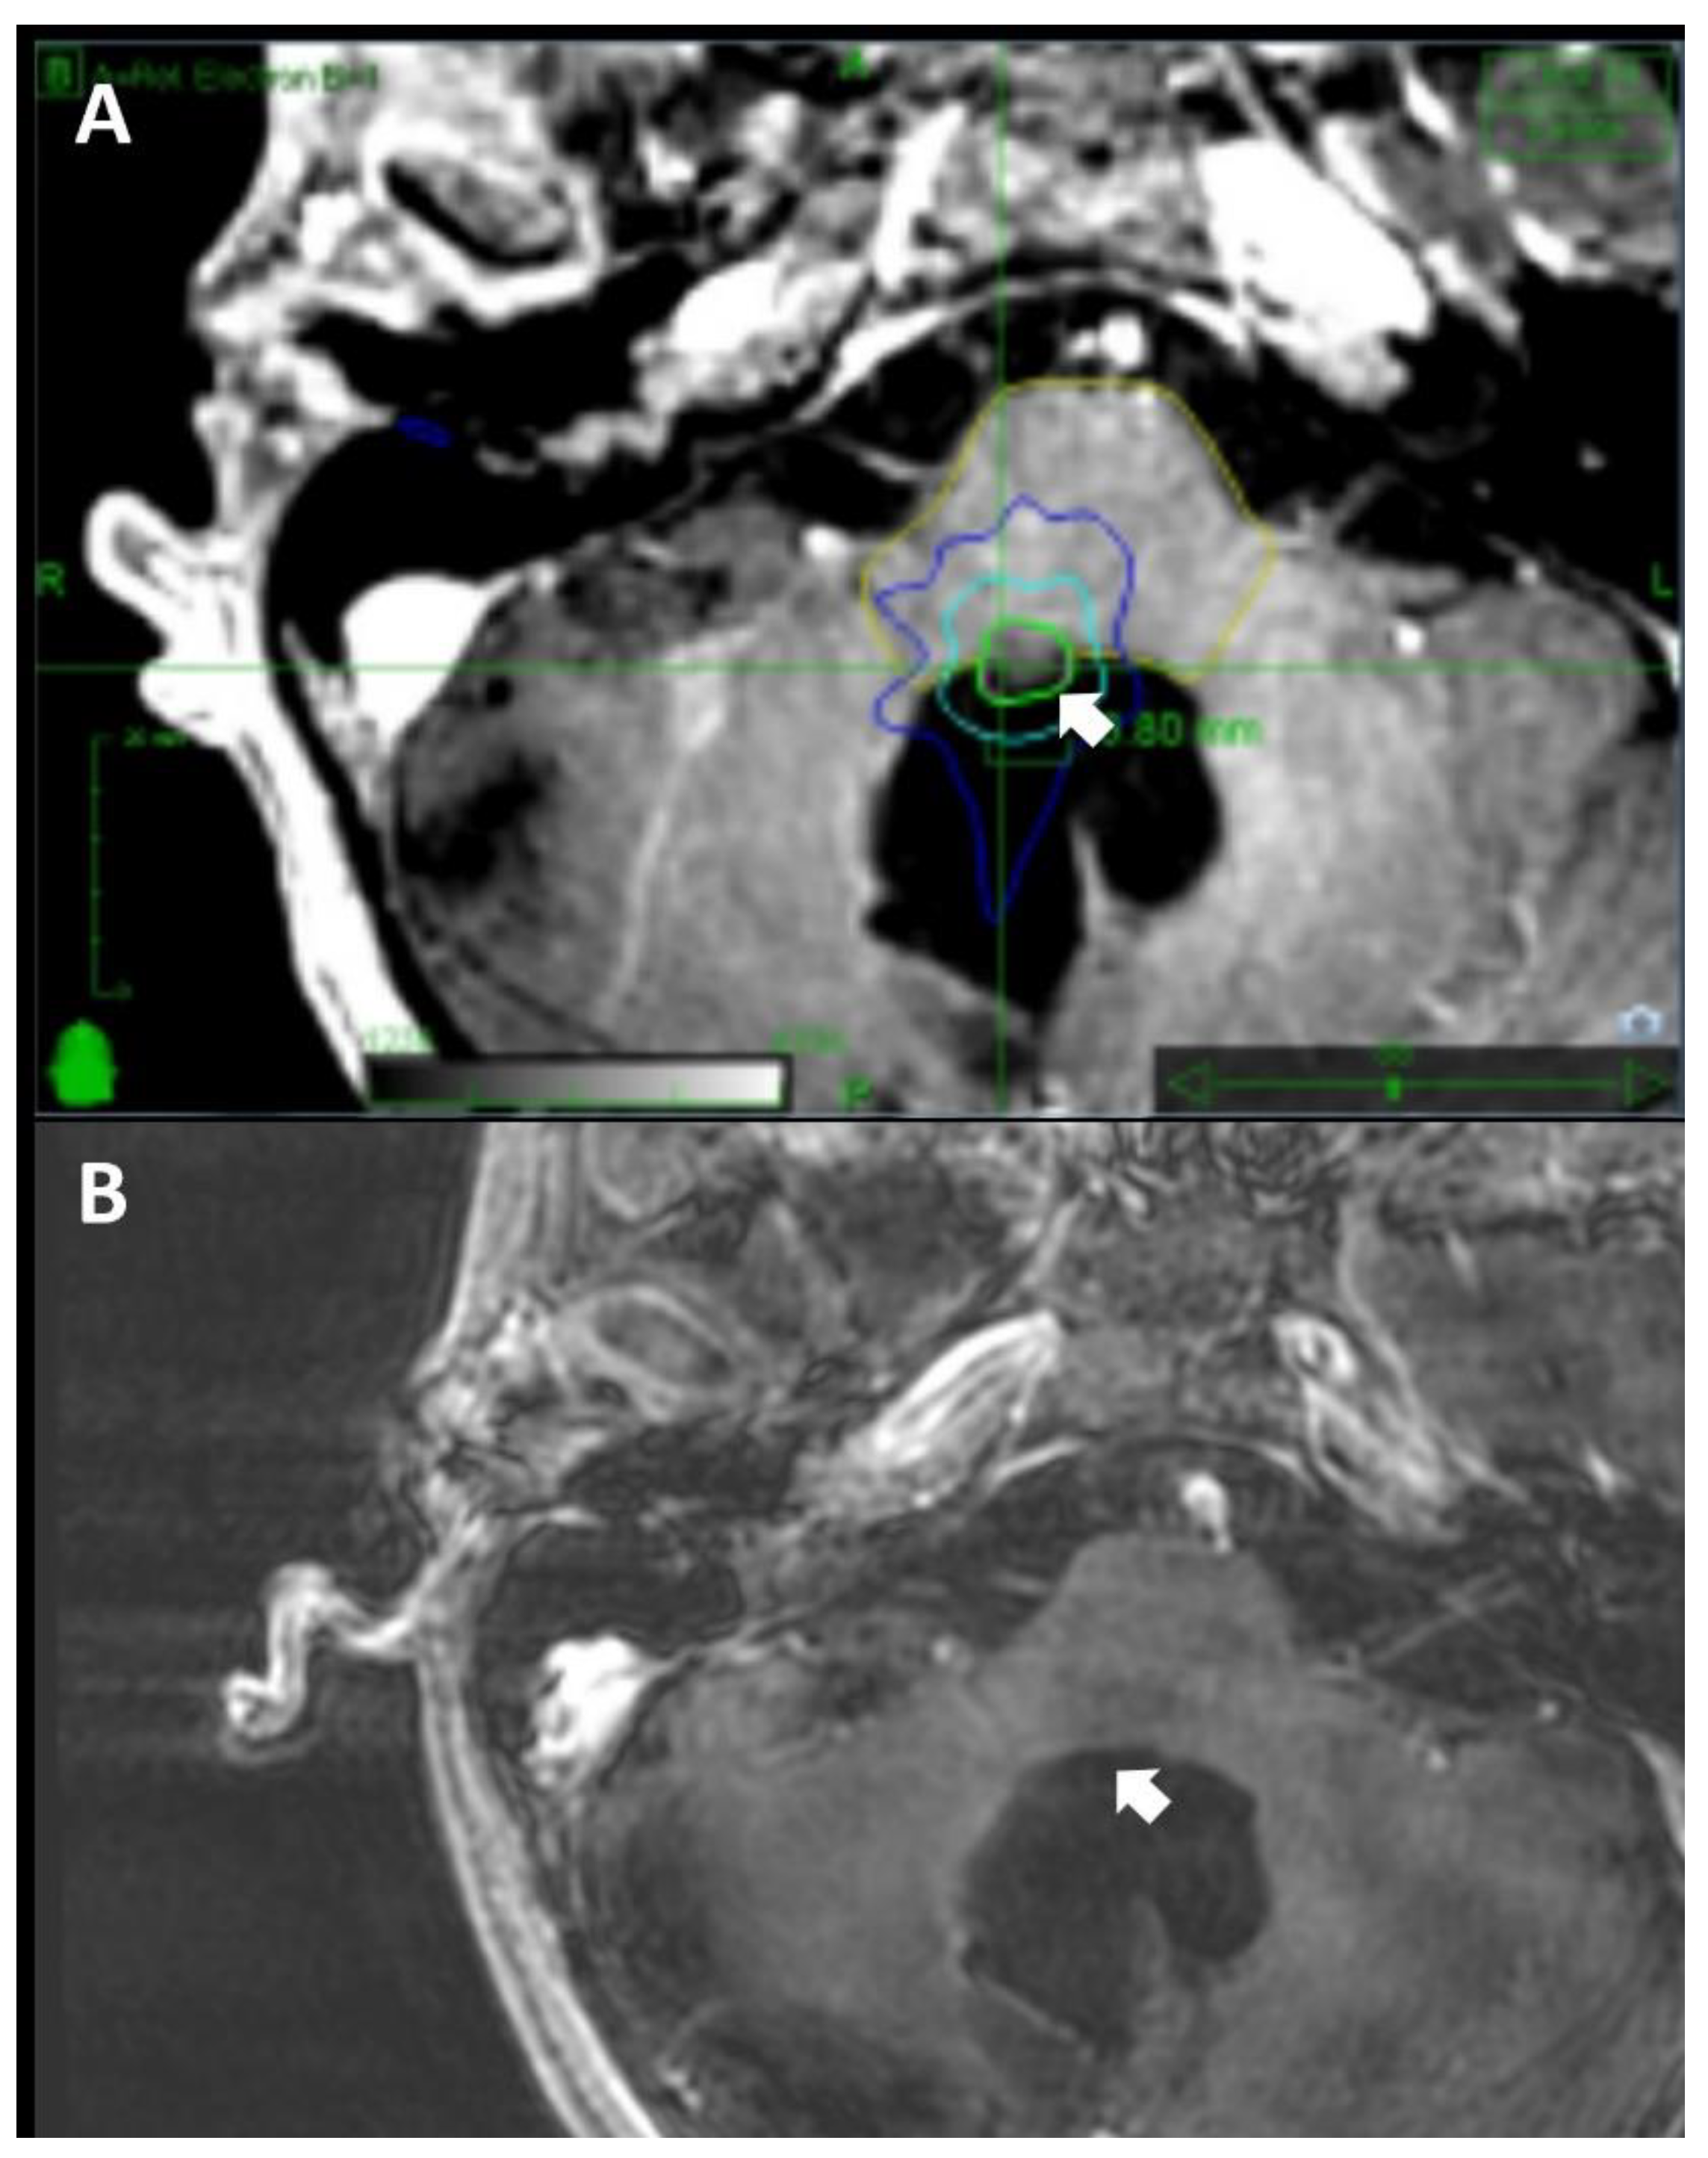

Figure 2. Comparison of A. a baseline CyberKnife treatment plan and B. the most recent radiographic follow-up evaluation of a 11-year-old male patient with a cervicomedullary recurrent medulloblastoma status post surgical resection and adjuvant radiation therapy. A marginal dose of 18 Gy was delivered with the maximum dose of 24.16 Gy in a single fraction to 75% of the isodose line (A). A substantial reduction in tumor size was evident in the 41-month follow-up MRI (B).